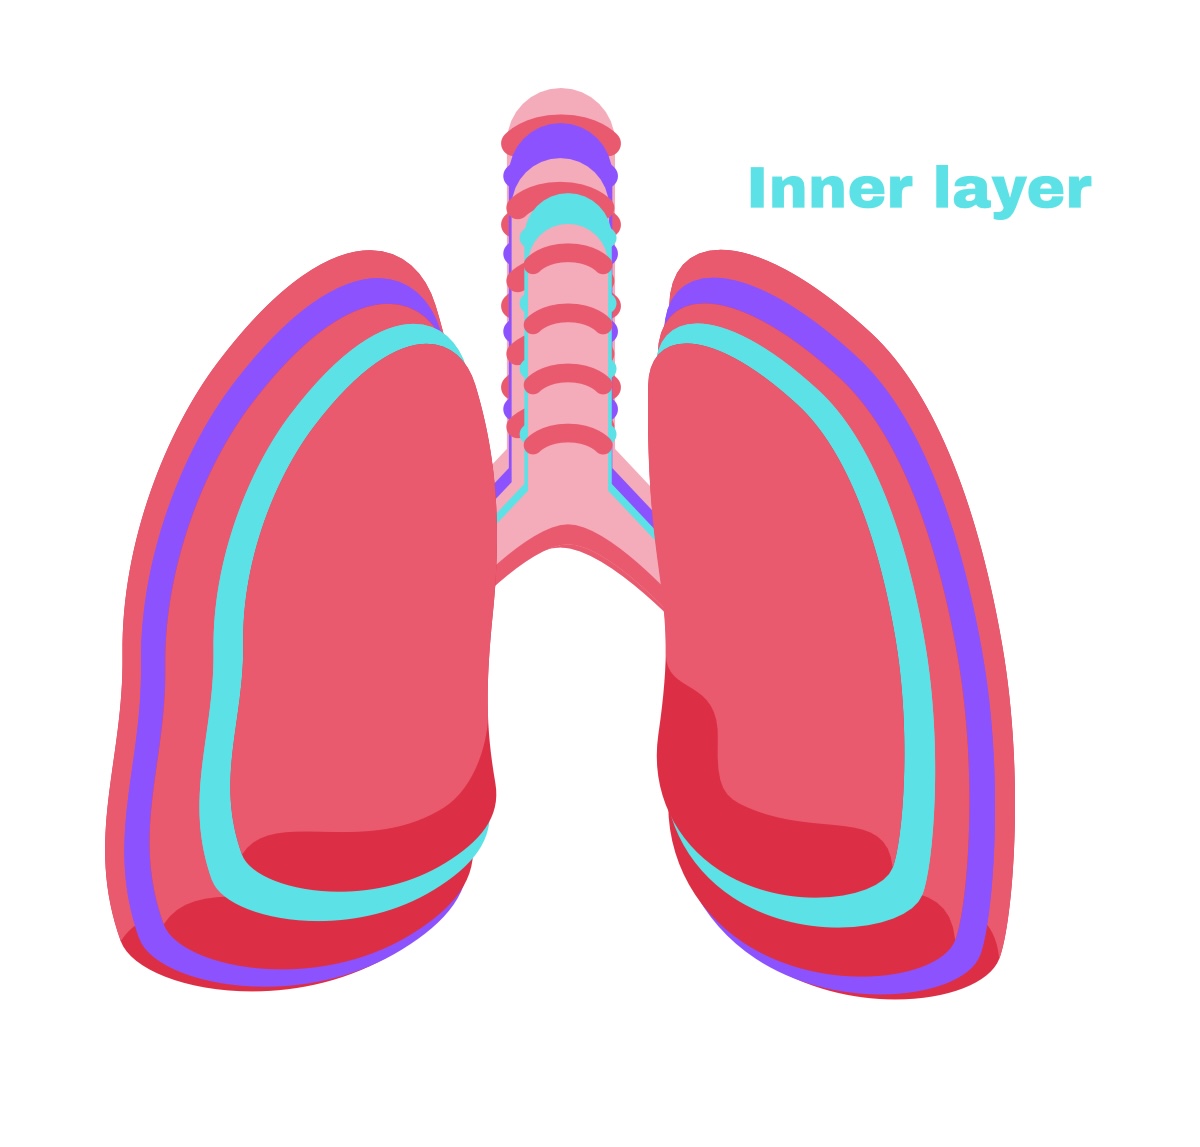

Visceral pleura

Deep layer (surface of organ)